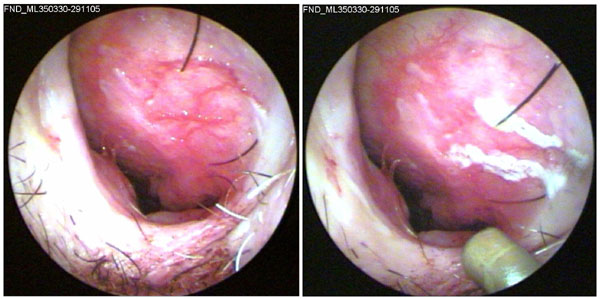

JFC Otitis media supurativa crónica. Colesteatoma.

JFC Otitis media crónica colesteatomatosa.